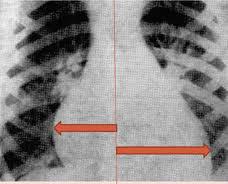

Диагностика кардитов нередко бывает затрудненной и требует от врача особого внимания. Заболевание имеет немало схожих симптомов с другими патологиями сердечно-сосудистой системы, например, с аритмией экстракардиального происхождения, ревматизмом, опухолевыми процессами в миокарде, пороками сердца, митральным стенозом.